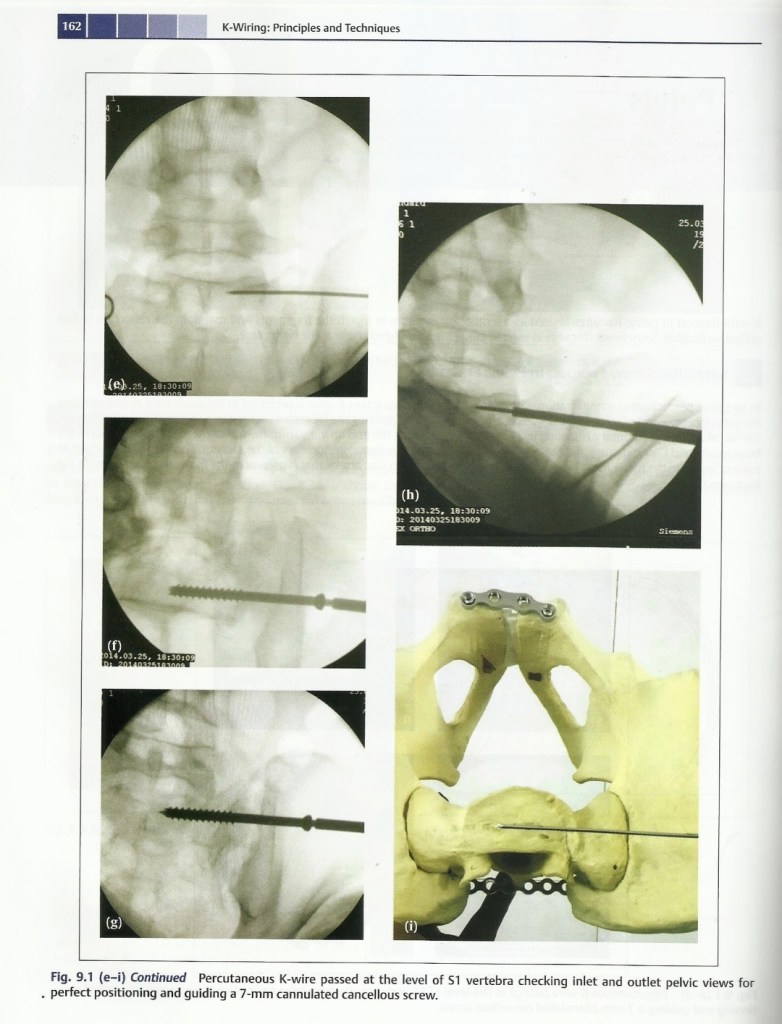

Lecture Pelvis fracture